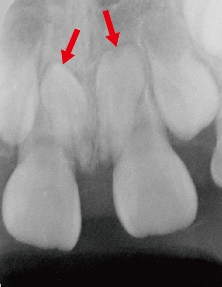

図1 上顎正中埋伏過剰歯のレントゲン写真(矢印)

骨内に2歯、上下が逆転(逆性)して埋伏している。過剰歯の好発部位でもある